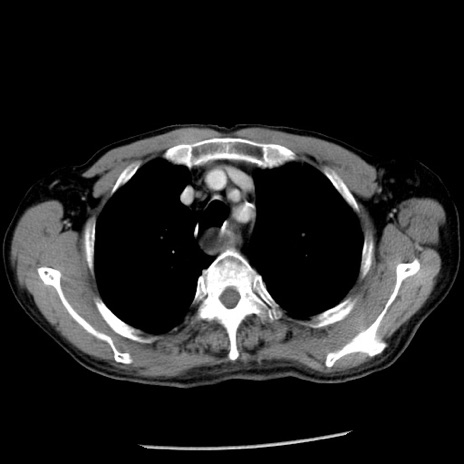

症例26(横断像)

【症例】80歳代男性

【主訴】嘔吐

【現病歴】昨晩2回嘔吐あり、今朝になっても嘔吐あり。来院。

【既往歴】胃潰瘍

【身体所見】意識清明、BT 37.6℃、BP 166/95mmHg、HR 100bpm、SpO2 97%、腹部:平坦・軟、腸蠕動音聴取良好、圧痛なし。

【データ】WBC 21900、CRP 1.46